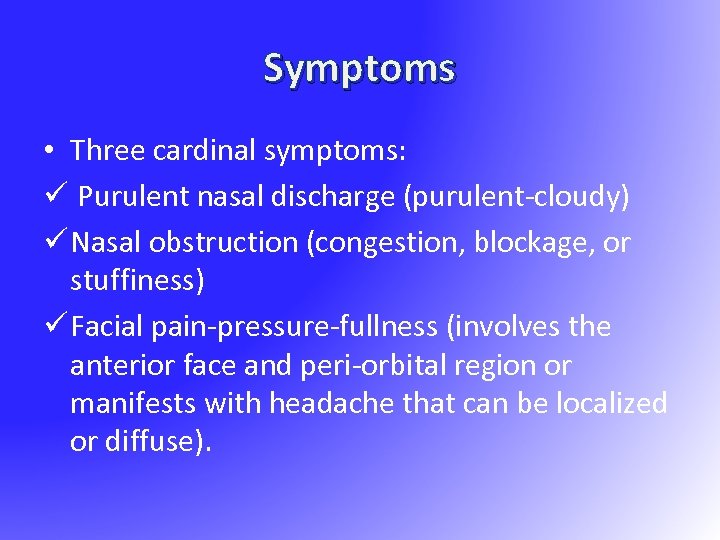

Symptoms • Three cardinal symptoms: ü Purulent nasal discharge (purulent-cloudy) ü Nasal obstruction (congestion, blockage, or stuffiness) ü Facial pain-pressure-fullness (involves the anterior face and peri-orbital region or manifests with headache that can be localized or diffuse).

Symptoms • Three cardinal symptoms: ü Purulent nasal discharge (purulent-cloudy) ü Nasal obstruction (congestion, blockage, or stuffiness) ü Facial pain-pressure-fullness (involves the anterior face and peri-orbital region or manifests with headache that can be localized or diffuse).